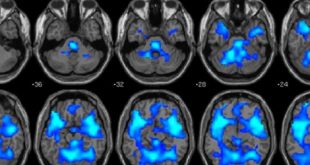

ادامهی نوشتهتاثیر متفاوت مراقبه بر شبکه های مغزی مراقبه کنندگان کهنه کار و نوآموز

نوروسافاری | تمرینات روانی مثل مراقبه ذهن آگاهی (پذیرش آگاهی از لحظه حال) نشان داده شده که شبکه های مغزی را تغییر میدهد و بهزیستی هیجانی و بدنی را بهبود میدهد. ولیکن پژوهشگران هنوز درحال کشف این مسئله هستند که چنین تمرین هایی چطور مغز را تغییر میدهند و …